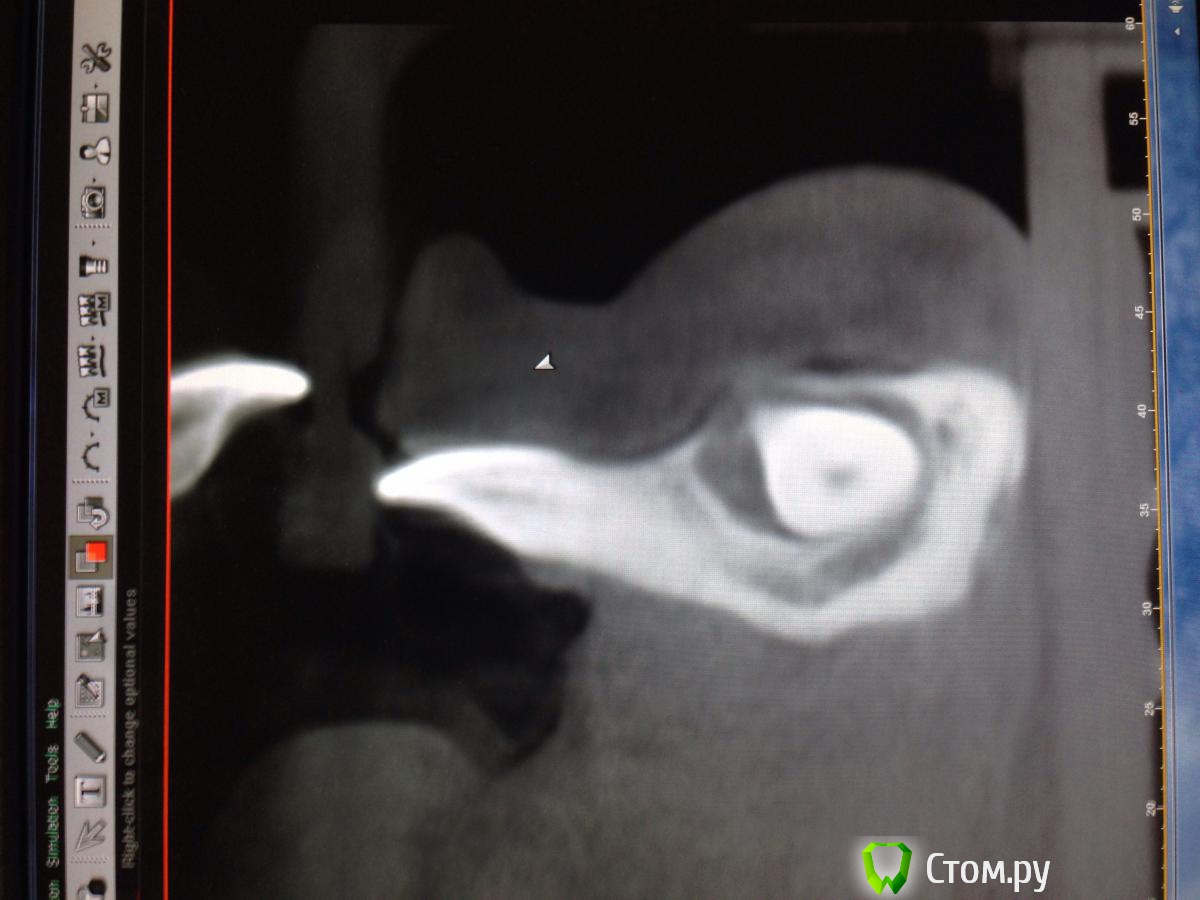

Opimar Опубликовано 29 ноября, 2013 Поделиться Опубликовано 29 ноября, 2013 Прошу совета по тактике лечения. Ортодонты привели пациента, 43 надо удалять. Впринципе ничего такого я не вижу, но все-таки как грамотно поступить взяться амбулаторно или направить в стационар. План лечения: Внутрибороздковый пошире с отслойкой передней поверхности подбородка ну и бор машиной фрагментировать зуб и удалить, либо без фрагментации если так пойдет. Швы, антибиотики, холод. Ну и предупредить о возможном онемении и травме резцов. Ссылка на комментарий

Alexey Doc Опубликовано 29 ноября, 2013 Поделиться Опубликовано 29 ноября, 2013 Амбулаторное удаление.Вот только дизайн разреза нужно првильный выбрать!не думаю что втутрибороздковый разрез создаст условия для оптимального доступа, да и отслойка при нем будет на большой площади. я бы сделал линейный ниже уровня переходной складки , если он не будет проходить над планируемым костным дефектом. 3 Ссылка на комментарий

kriokov Опубликовано 29 ноября, 2013 Поделиться Опубликовано 29 ноября, 2013 Разрез послойный:сперва слизистую в области переходной, затем мышцы (ушивание в обратной последовательности). Отверстие на уровне (приблизительно) средины корня. Три сегмента.Удаляете средний, дальше по ситуации.В дефект-от коллагена до графта.Давящая повязка снаружи.если доктор не делал низких доступов, трудно будет сообразить по первой как ушиться. Может уж чуть выше разрез сделать по нижней границе прикрепленной если прикрепленной хватает? И риск рецессии меньше чем при сулькулярном, и одним блоком надкостницу с мышцами поднимет, и ушьется почаще но в один слой, и ветки ментального в мягких тканях если чего целые будут.? 3 Ссылка на комментарий

rivezico Опубликовано 29 ноября, 2013 Поделиться Опубликовано 29 ноября, 2013 опять же, чем дистальнее - тем аккуратнее в этой области Ссылка на комментарий